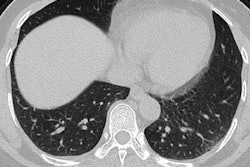

47-year-old Chinese man with two-day history of fever, chills, productive cough, sneezing, and fatigue who presented to emergency department. A and B: Initial CT images obtained show small round areas of mixed ground-glass opacity and consolidation (rectangles) at level of aortic arch (A) and ventricles (B) in right and left lower lobe posterior zones. C and D: Follow-up CT images obtained two days later show progression of abnormalities (rectangles) at the level of aortic arch (C) and ventricles (D), which now involve right upper and right and left lower lobe posterior zones. Images courtesy of the American Journal of Roentgenology.The three diseases share the following symptoms: fever, dyspnea, malaise, myalgia, and headache; all three also tend to show ground-glass opacity, consolidation, or both on imaging, while lymphadenopathy is not usually seen. Clinicians have been diagnosing COVID-19 in patients with these symptoms who recently traveled to China.

"An investigation of initial chest CT findings in 21 individuals with confirmed COVID-19 reported abnormal findings in 86% of patients, with a majority having bilateral lung involvement," the authors wrote.